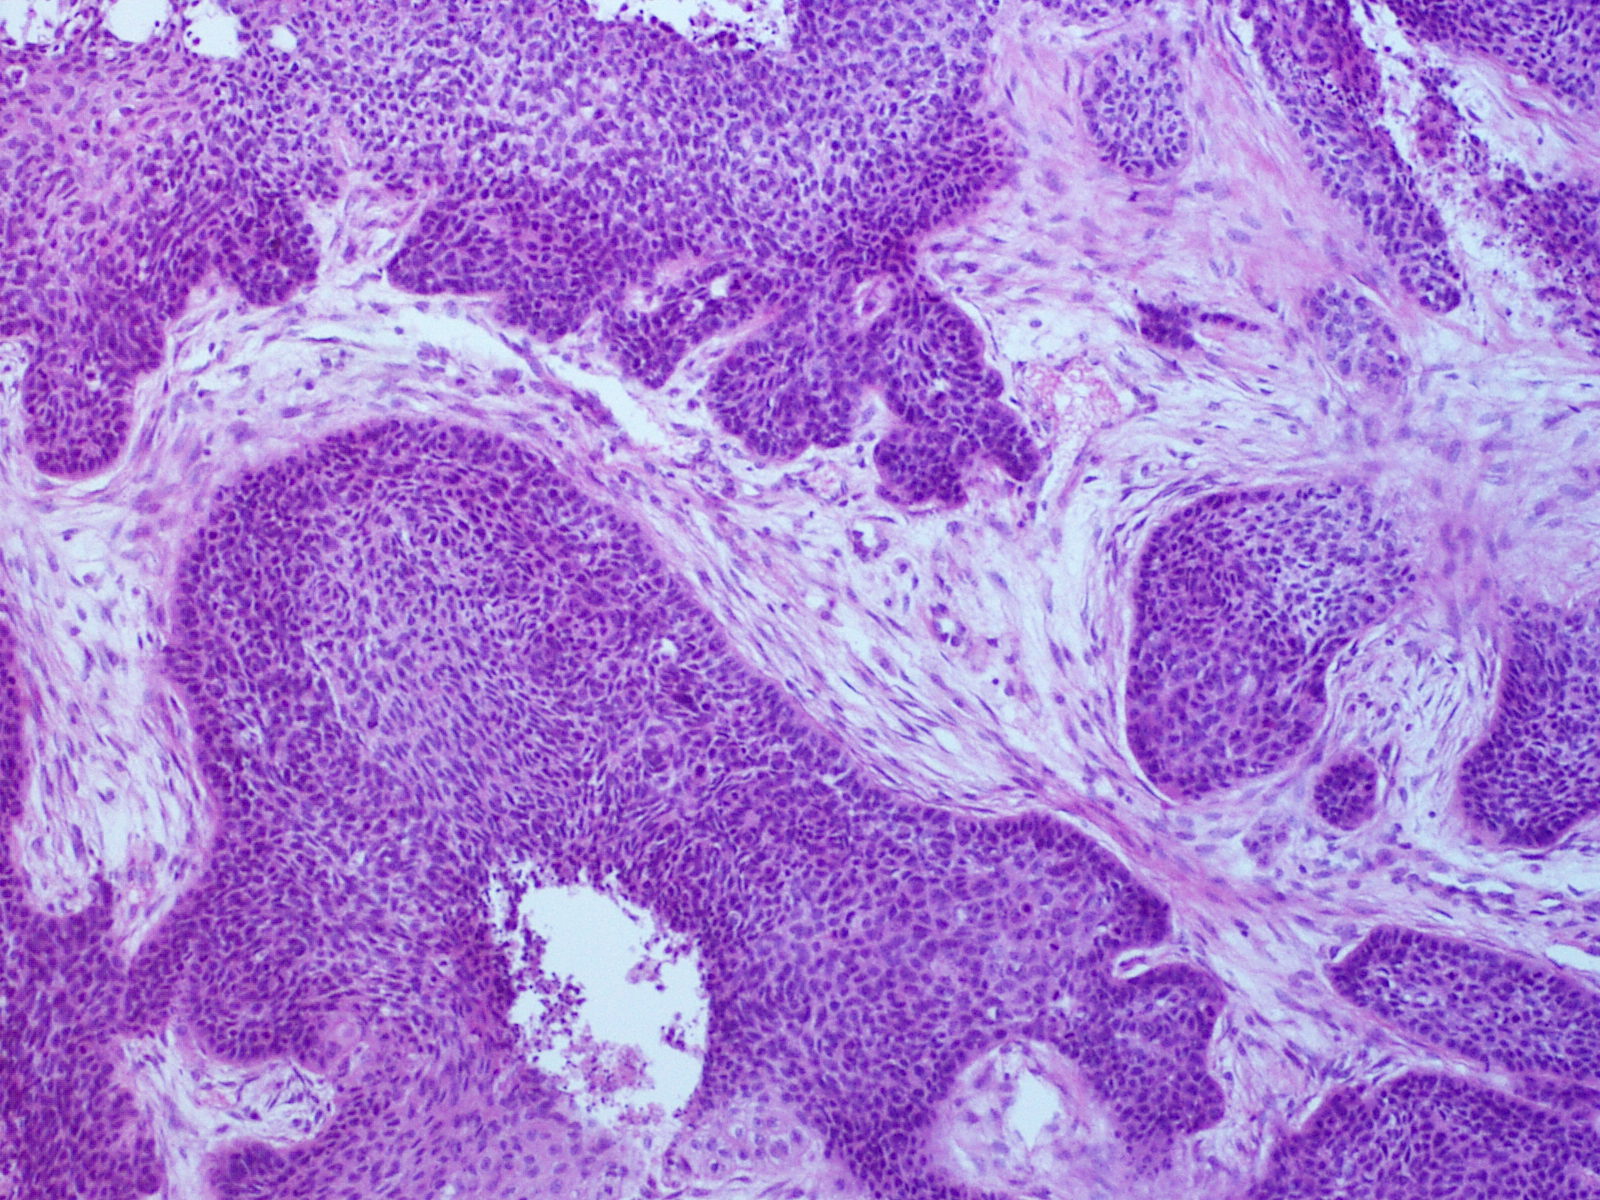

편평상피세포암(SCC)은 상피 계통의 암 줄기 세포가 반복적이고 제어되지 않게 분열하면서 시작된다.[19][20][21] 이 암은 신체 여러 부위를 덮고 있는 편평한 세포인 편평 상피 세포에서 발생하며, 그 중 일부는 각질 세포이다. 암세포가 축적되면 비정상 세포의 미세한 초점이 생기는데, 초기에는 기원 세포가 있던 조직 내에 국한된다. 이러한 상태를 편평상피세포 상피내암종이라고 한다.

병변이 성장하여 인접 구조를 파괴하고 침투하면 "침윤성" 편평상피세포암이라고 한다. 침윤성 암은 다른 장기로 퍼져 전이를 일으킬 수 있다.

병력, 신체 검사 및 의학 영상은 편평상피세포암을 시사할 수 있지만, 일반적으로 조직병리학적 생검을 통해 진단을 확정한다. TP63 염색은 편평상피세포암의 주요 조직학적 표지자이다. 또한 TP63은 편평 세포의 정체성을 확립하는 데 필수적인 전사 인자이다.[18]